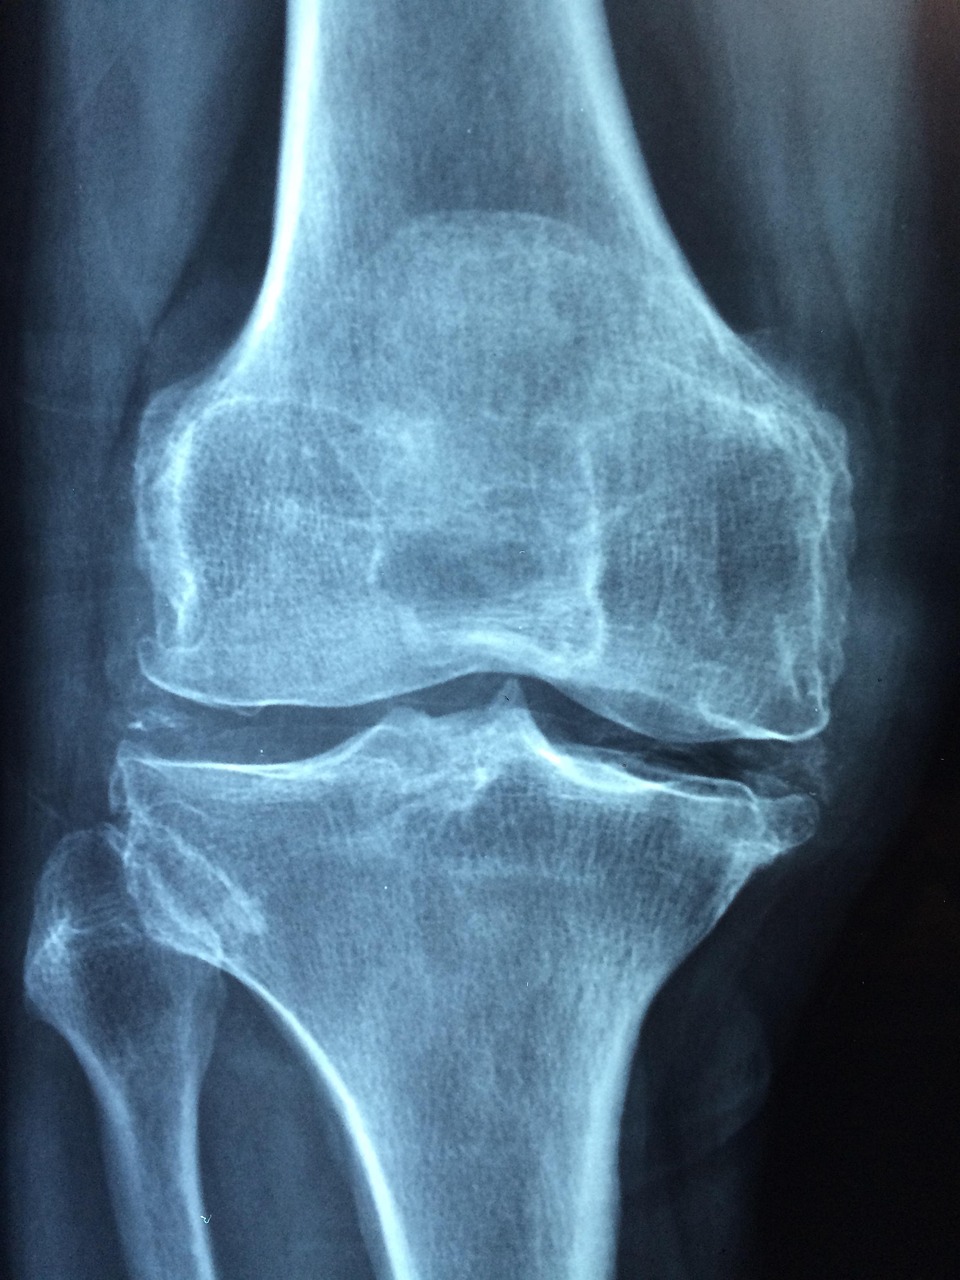

60대 이후에도 일상생활에서 활발하게 움직이는 분들이 많습니다. 자녀를 돌보거나 가벼운 일을 계속하거나, 여행과 등산 등 여가 활동을 즐기는 경우도 흔합니다. 하지만 이처럼 활동량이 많은 60대일수록 오히려 관절에 무리를 주기 쉽습니다. 관절 건강은 한 번 손상되면 회복이 어렵기 때문에, ‘무리하지 않기’는 가장 중요한 원칙입니다. 먼저, 장시간 한 자세로 있는 것을 피해야 합니다. 오랜 시간 앉아 있거나 서 있는 습관은 무릎, 고관절, 발목 등에 부담을 줄 수 있으므로, 30~40분 간격으로 자리에서 일어나 스트레칭을 해주는 것이 좋습니다. 가벼운 걷기나 허리 돌리기, 무릎 펴기 같은 간단한 동작도 큰 도움이 됩니다. 또한, 무거운 물건을 들거나 갑작스러운 동작은 피해야 하며, 계단 오르내리기보다는 가능하면 엘리베이터나 에스컬레이터를 이용하는 것이 관절 보호에 효과적입니다. 특히 무릎 관절에 무리가 가는 쪼그려 앉기, 무릎 꿇기 자세는 가급적 삼가야 합니다. 생활 속에서도 관절을 보호할 수 있는 다양한 실천이 가능합니다. 예를 들어, 바닥 생활을 줄이고 의자 생활로 전환하는 것, 적절한 쿠션이 있는 신발을 착용하는 것 등이 있습니다. 충격 흡수가 가능한 신발이나 실내 전용 슬리퍼를 신으면 관절에 가해지는 충격을 줄일 수 있습니다. 마지막으로, 활동 전후에 충분한 준비운동과 마무리 스트레칭을 하는 것도 중요합니다. 무리 없이 생활하는 습관이 관절염 예방의 시작입니다.

운동은 관절염을 예방하고 개선하는 데 있어 가장 중요한 루틴 중 하나입니다. 특히 60대 이후에는 유연성과 근력을 함께 관리해야 하기 때문에, 무리하지 않으면서도 꾸준히 할 수 있는 운동을 선택하는 것이 핵심입니다. 첫 번째로 추천할 수 있는 운동은 걷기입니다. 하루 30분 정도 빠르지 않은 속도로 걷는 것만으로도 관절 주변 근육이 강화되고 체중 조절에 도움이 됩니다. 단, 단단한 콘크리트 바닥보다는 흙길이나 트랙처럼 충격이 덜한 장소에서 걷는 것이 좋습니다. 수중 운동도 관절에 무리를 주지 않으면서 운동 효과를 볼 수 있는 방법입니다. 물속에서는 체중 부담이 줄어들기 때문에 무릎이나 고관절에 부담 없이 움직일 수 있습니다. 수중 스트레칭이나 아쿠아로빅 같은 운동은 관절염이 있는 사람들에게도 적합합니다. 스트레칭과 요가는 관절 유연성을 유지하고 혈액순환을 도와 통증 완화에 도움이 됩니다. 특히 아침이나 저녁 시간에 15분 정도 꾸준히 해주는 것이 좋습니다. 단, 무리한 동작은 피하고 자신의 유연성에 맞게 천천히 진행해야 합니다. 근력 운동도 매우 중요합니다. 무릎과 고관절을 보호하려면 주변 근육을 강화해야 하기 때문에, 스쿼트나 런지, 레그레이즈와 같은 간단한 하체 근력 운동을 추천합니다. 집에서도 체중을 이용한 운동이 가능하며, 가벼운 아령이나 탄력 밴드를 활용해 점진적으로 강도를 조절할 수 있습니다. 운동 전후에는 반드시 스트레칭과 충분한 수분 섭취를 병행해야 부상 없이 건강하게 관절을 관리할 수 있습니다.